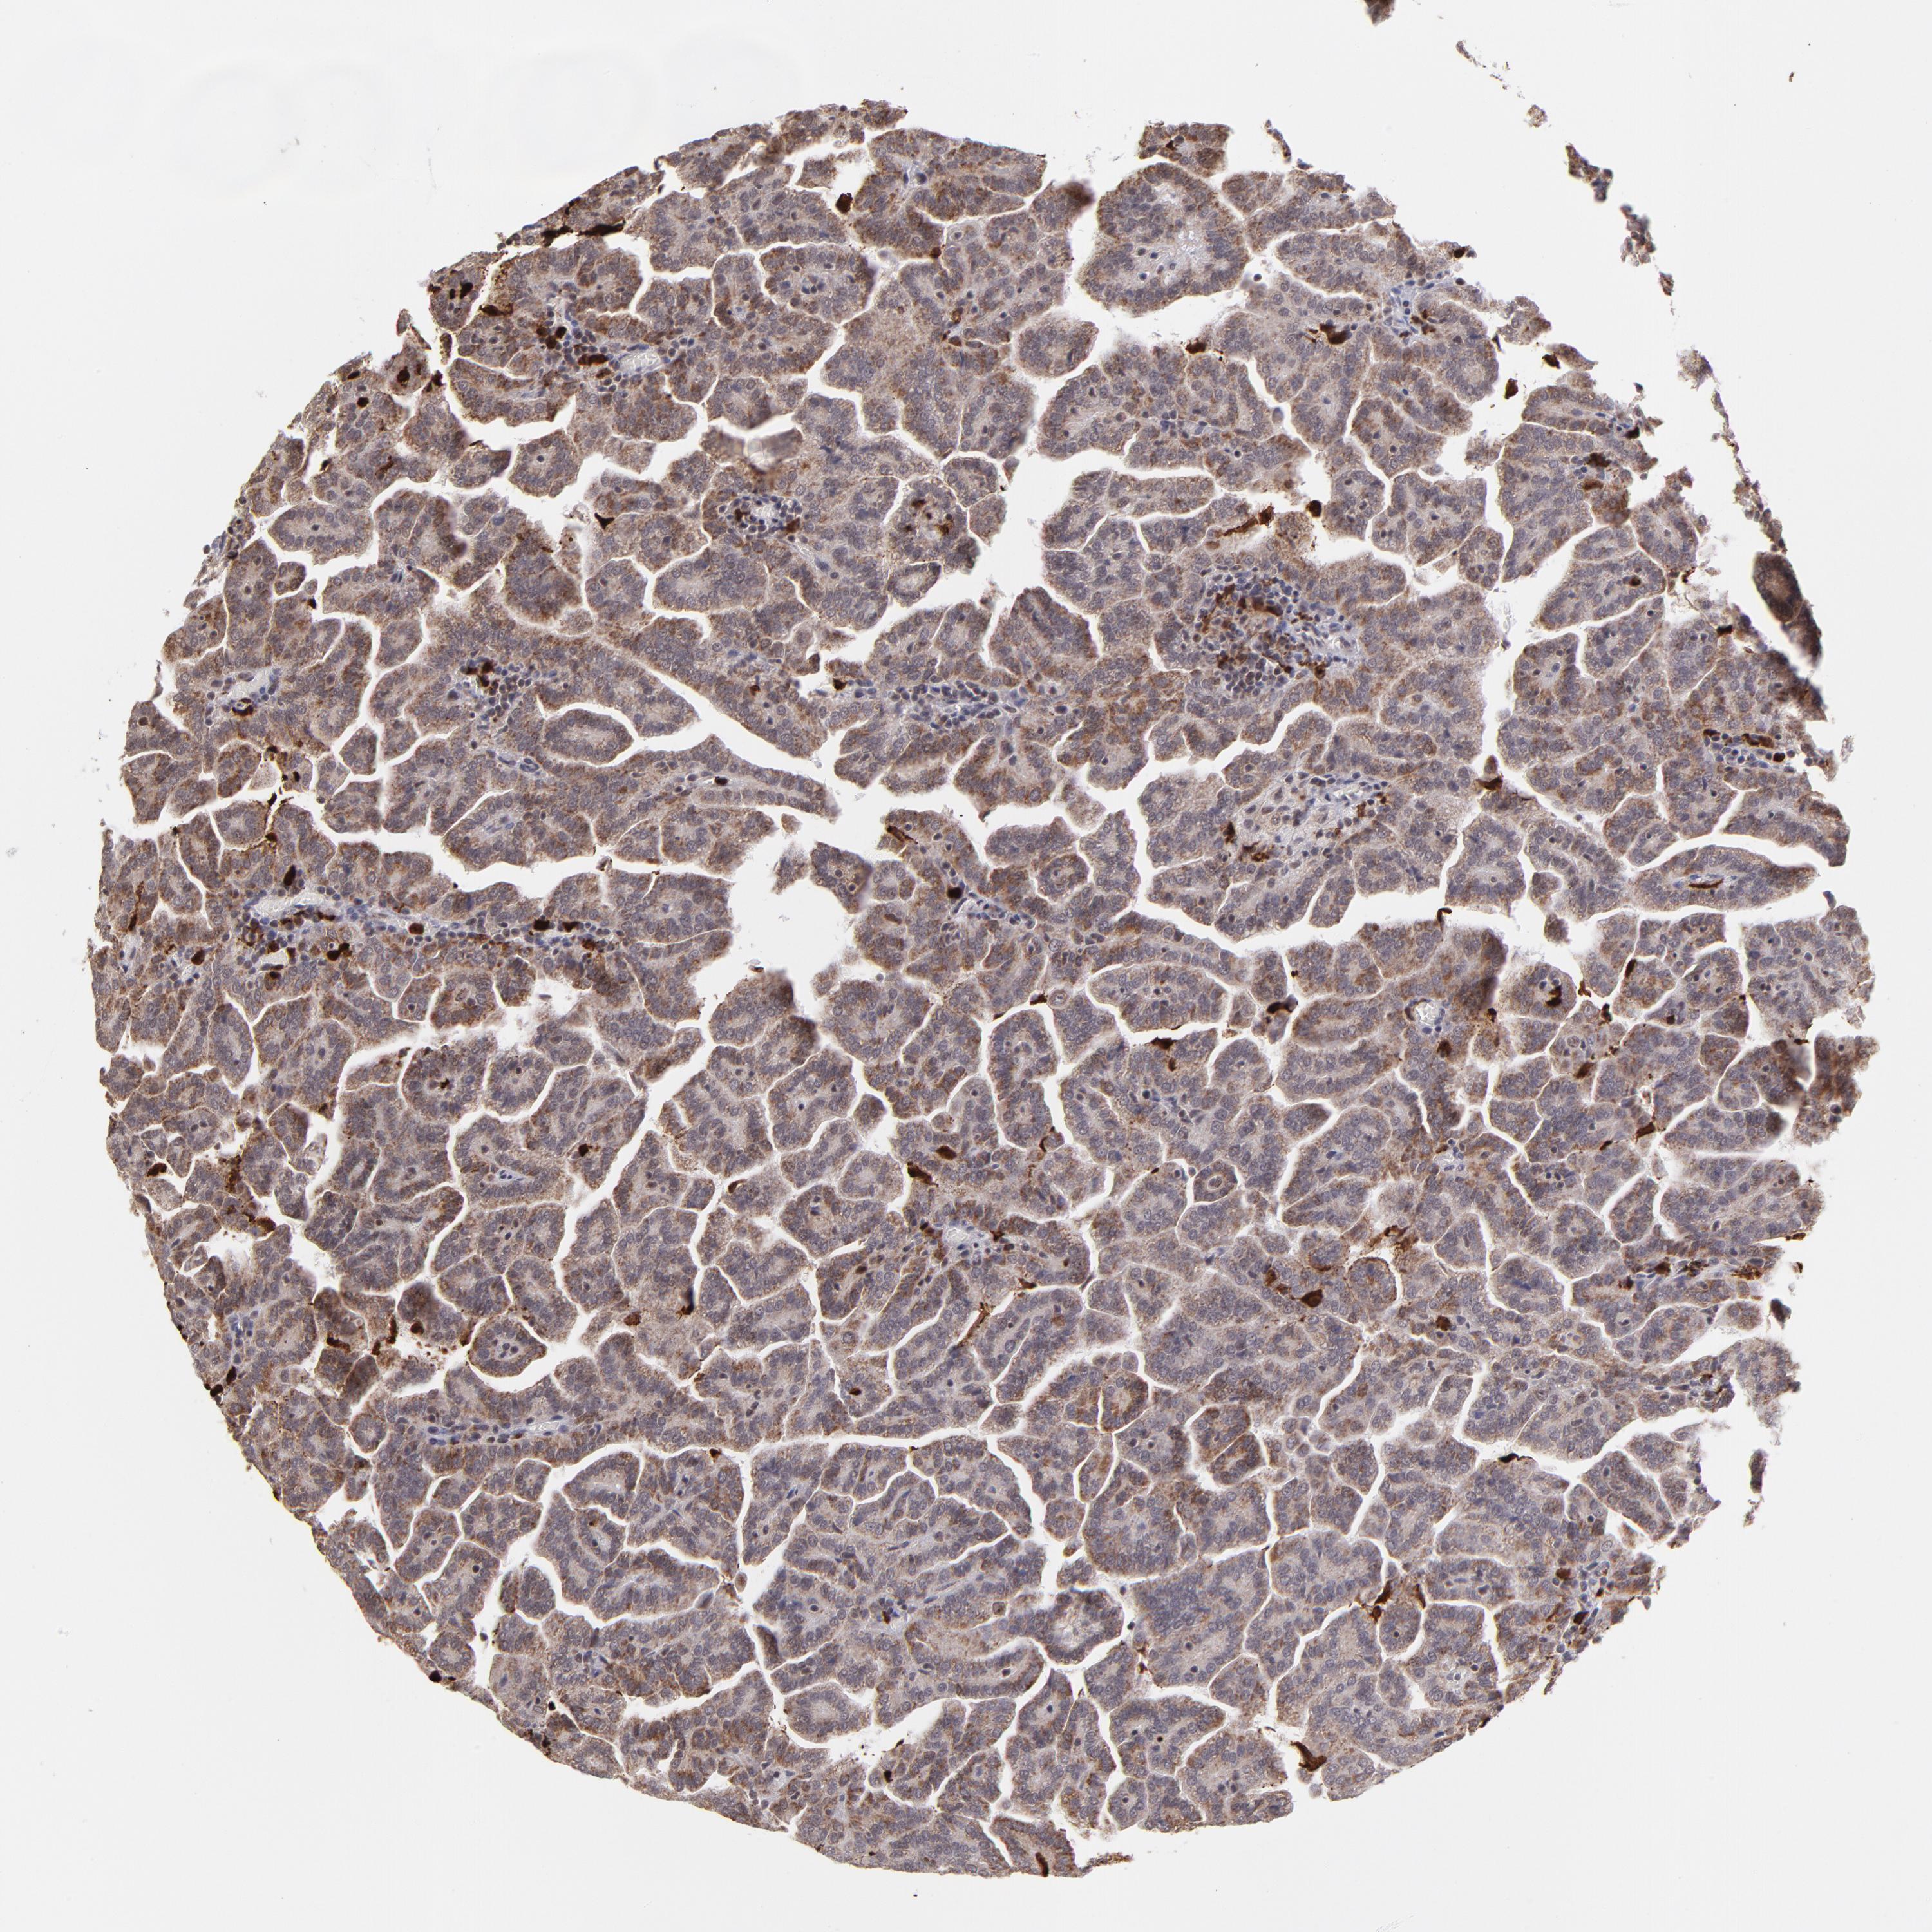

KIDNEY RENAL CLEAR CELL CARCINOMA (VALIDATION) - Interactive survival scatter ploti

The Survival Scatter plot shows the clinical status (i.e. dead or alive) for all individuals in the patient cohort, based on the same data that underlies the corresponding Kaplan-Meier plots. Patients that are alive at last time for follow-up are shown in blue and patients who have died during the study are shown in red.

The x-axis shows the expression levels (FPKM) of the investigated gene in the tumor tissue at the time of diagnosis. The y-axis shows the follow-up time after diagnosis (years). Both axes are complimented with kernel density curves demonstrating the data density over the axes. The top density plot shows the expression levels (FPKM) distribution among dead (red) and alive patients (blue). The right density plot shows the data density of the survived years of dead patients with high and low expression levels respectively, stratified using the cutoff indicated by the vertical dashed line through the Survival Scatter plot. This cutoff is automatically defined based on the FPKM cutoff that minimizes the p-score. The cutoff can be changed by dragging the vertical line or by entering a cutoff value in the square labeled "Current cut-off".

Under the Survival Scatter plot the p-score landscape (black curve; left axis) is shown together with dead median separation (red curve; right axis). Dead median separation is the difference in median mRNA expression between patients who have died with high and low expression, respectively. It is calculated as follows: median FPKM expression of dead patients with high expression - median FPKM expression of dead patients with low expression. This is intended to aid the user in visually exploring custom cutoffs and the associated p-scores and dead median separation.

Individual patient data is displayed and can be filtered by clicking on one or more of the category buttons on the top of the page. Categories describing expression level and patient information include: high, low, alive, dead, female, male and tumor stages. The scale of the x-axis can be toggled between linear and log-scale by clicking on the "x log" button. Mouse-over function shows TCGA ID, patient information and mRNA expression (FPKM) for each patient.

& Survival analysisi

Kaplan-Meier plots summarize results from analysis of correlation between mRNA expression level and patient survival. Patients were divided based on level of expression into one of the two groups "low" (under cut off) or "high" (over cut off). X-axis shows time for survival (years) and y-axis shows the probability of survival, where 1.0 corresponds to 100 percent.

ZFX is not prognostic in Kidney Renal Clear Cell Carcinoma (validation)

Best expression cut offi

: 10.31

P scorei

N/A

5-year survival highi

For melanoma and glioma, 3-year survival is shown.

5-year survival lowi

Average pTPM 11.2

Number of samples 100